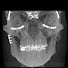

Mouth Cancer Treatment without Surgery